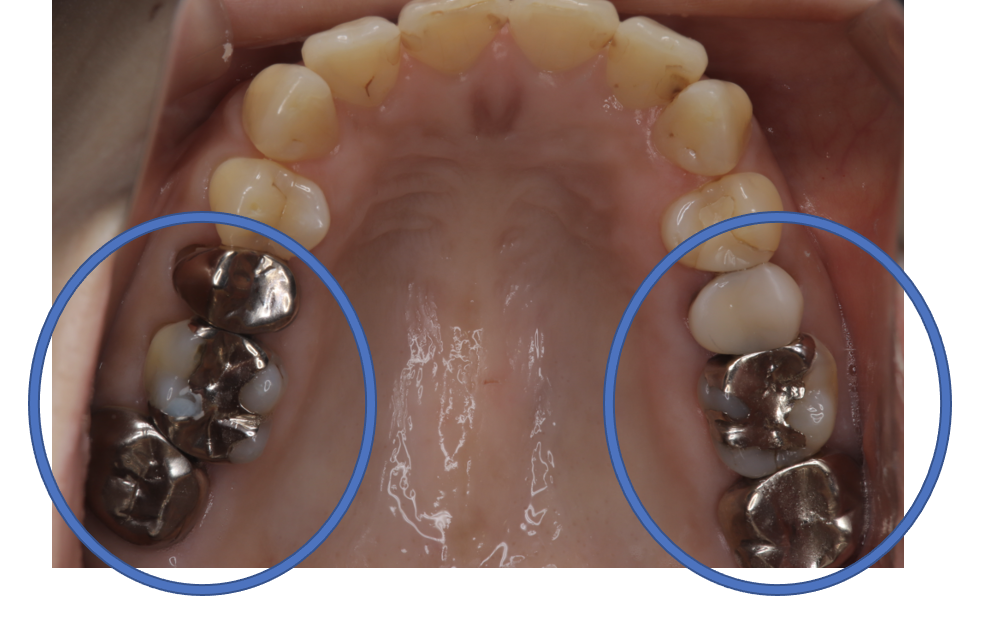

クラウンフルジルコニア

フルジルコニアCr 28 No.72

Before

After

| 治療方法 | フルジルコニアCr 虫歯などで失った歯質を天然歯と同じ色・質感のセラミックの一種であるジルコニア(人工ダイヤモンド)で補う治療法。 |

| 治療のデメリット | 変色がなく耐久性の高い治療ですが、歯周病や二次虫歯を予防するためには歯科医院での定期的なメインテナンスが大切です。 |

| 費用 | ¥89,000×2本=¥178,000 |

| 通院回数 | 1ヶ月〜6ヶ月 |

| 備考 | 院長より 銀歯の内部に虫歯が進行してしまっていたケースです。中を開けて見てみると、外から想像するよりもはるかに虫歯が広がってしまっていました。残存歯質がかなり薄く弱くなってしまったので、ジルコニアで被せて守ってあげています。 |